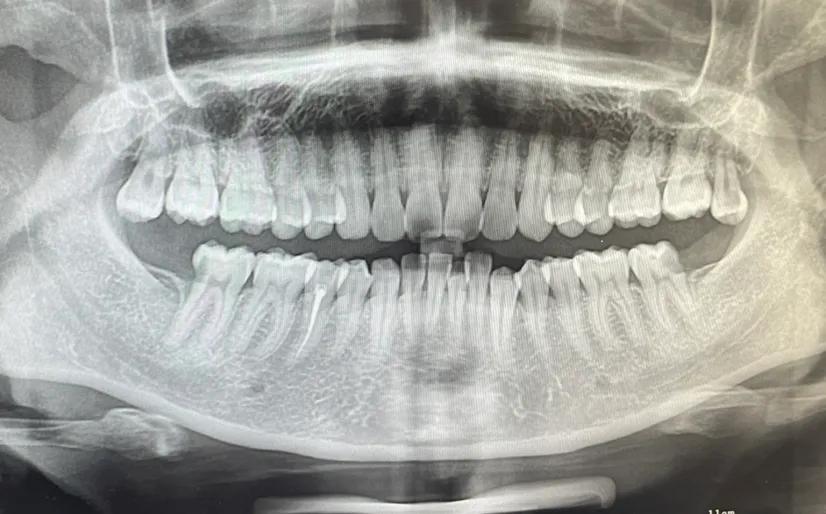

拓展知識(shí):種植牙中間一般要拔多少顆

這個(gè)要根據(jù)患者的實(shí)際情況,不同的患者能承受的不同 。建議到正規(guī)口腔科醫(yī)院【北京三級口腔醫(yī)院】根據(jù)患者的情況在決定。患者可以在恢復(fù)牙齒咀嚼功能的前提下兼顧牙齒美觀,針對全口牙齒缺失的患者是可以通過全口種植來恢復(fù)牙齒功能與美觀的,種牙點(diǎn)擊申領(lǐng)種牙補(bǔ)貼

傳統(tǒng)種植牙方式需要二次手術(shù)和3-6個(gè)月修復(fù)期,這對于怕麻煩追求率的市民或許不太合適,可選擇“即拔、即種、即用”的用種植方案,該技術(shù)是英國愛丁堡大學(xué)贊安南博士帶領(lǐng)實(shí)施的,根據(jù)患者牙槽骨密度、高度、寬度,自動(dòng)避開血管和神經(jīng),以1微米的精度種植牙根,做到即拔即種,一次完成手術(shù)。

一般連續(xù)牙齒缺失的情況是可以進(jìn)行一次種植牙修復(fù)的,并且不需要種植多顆種植體,一般需要連續(xù)缺失5顆或者4顆牙,只需要2到3個(gè)種植體就足夠,在費(fèi)用上也省了不少錢,如果有需求一定要選擇正規(guī)專業(yè)點(diǎn)的口腔機(jī)構(gòu)進(jìn)行缺失牙種植調(diào)節(jié)。

一次可以種植2到3顆,但拔牙一次只能拔一顆,等徹底消炎好了才能拔第二顆。

看什么情況才能做決定,正常能做3顆牙左右,特殊情況滿口牙一起種。